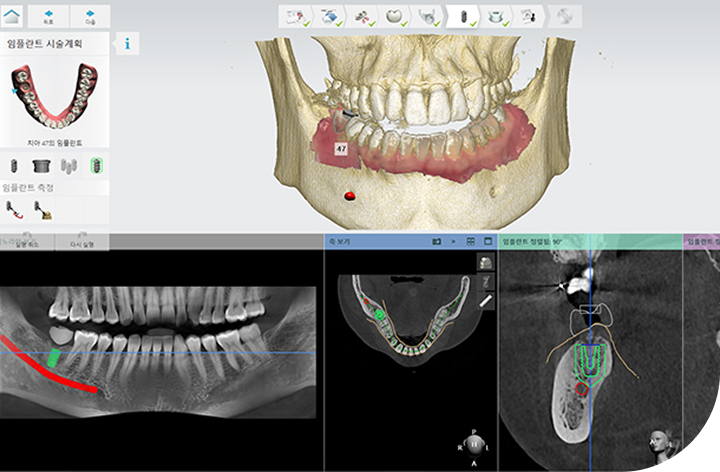

환자의 구강 정보를 디지털 데이터를 기반으로 3D 가상 모의 수술을

진행해 기존 방식 대비 수술 시간이 짧아 체력적 부담을 줄여주고

최소 절개로 통증 및 붓기 최소화로 면역력이 약하거나 회복력이 더딘

고령의 환자, 고혈압 당뇨 등 전신질환을 앓고 계신 분들도 부담없이 안전하게 수술받을 수 있습니다.

성공적인 임플란트 식립을 위해서는 정밀한 진단이 필수적입니다.

3D-CT, 구강 스캐너 등 다양한 디지털 장비를 이용하여

치아, 잇몸뼈, 신경 위치 등을 정확하게 파악해 수술 오차를 최소화하고,

통증 및 출혈을 줄여 더욱 안전하고 편안한 임플란트 식립이 가능합니다.

3D-CT를 통한 정밀 진단

3D-CT 분석을 통해 상악동 구조와

골 상태를 정확하게 진단합니다.